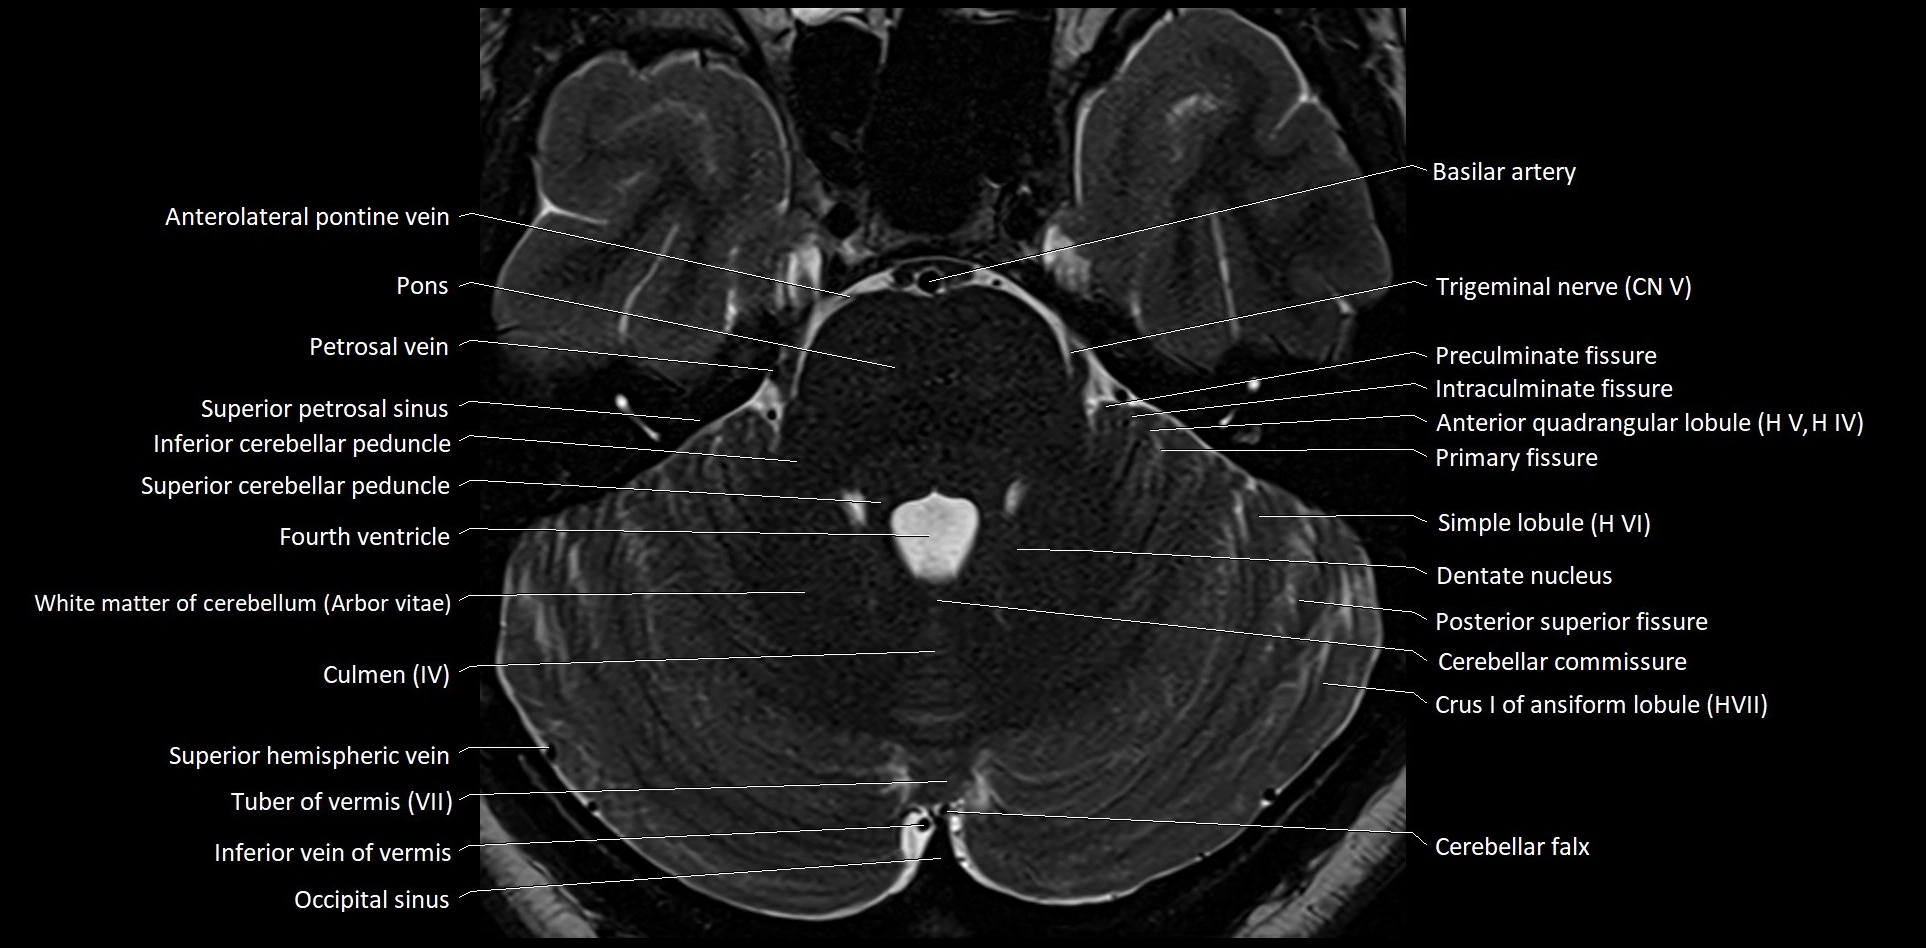

MRI images